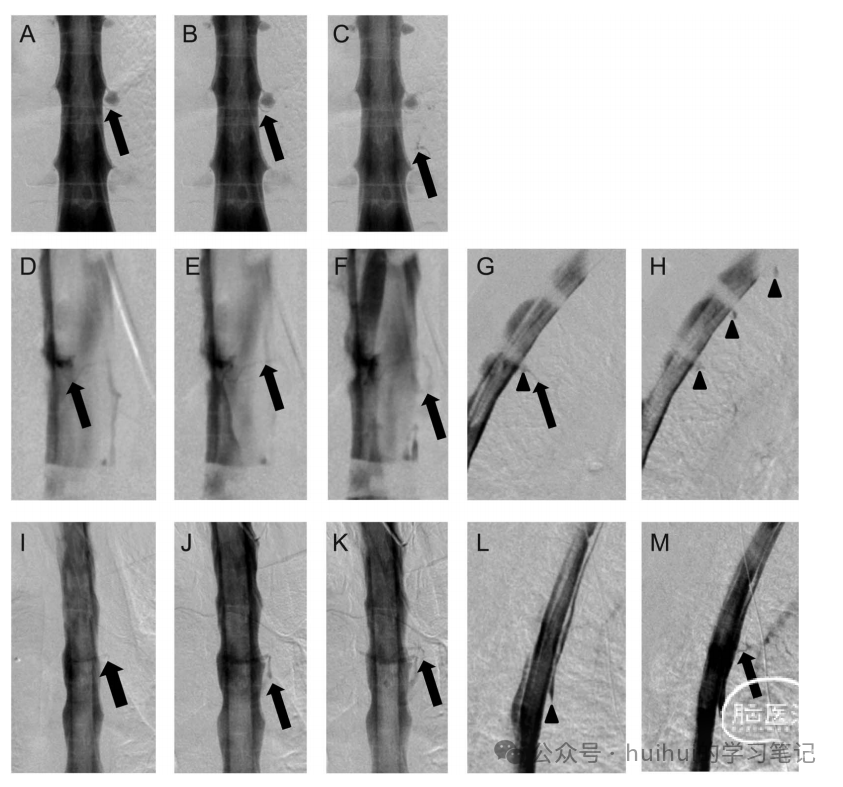

案例报告。案例1。一名52岁的女性指出,下半日头痛,颈部僵硬,肩胛间疼痛。神经系统检查正常。MRI显示硬脑膜增强及脑下垂。CT和磁共振(MR)脊髓造影显示多发胸椎囊肿,但未见脑脊液渗漏。脑脊液检查正常。卧床休息并不能缓解病情。DSM显示一个直接起源于左侧T-10囊肿的瘘管进入脊髓硬膜外静脉(图)。经皮注射纤维蛋白胶可缓解症状。

案例2。一名31岁的女性称她有直立性头痛、耳鸣和颈部僵硬。神经系统检查正常。MRI显示硬脑膜增强,脑下垂,垂体肿大。CT和MR脊髓造影显示广泛的脊髓腹侧硬膜外脑脊液收集。脑脊液检查正常。患者接受了多次硬膜外血贴,但症状持续存在。DSM显示T-2/3处腹侧脑脊液泄漏,患者接受手术修复,症状得到缓解。10个月后,症状复发,但CT脊髓造影未见脑脊液渗漏。DSM显示一个直接瘘管起源于左侧T-4神经根区域,进入脊髓硬膜外静脉(图)。腹侧脑脊液渗漏不再明显。手术时,硬膜外静脉扩张明显,发现左侧T-4神经根腋窝处有硬膜撕裂,并将其缝合,症状得以缓解。

案例3。一名48岁女性,体位性头痛、恶心、呕吐和颈部僵硬。神经系统检查正常。MRI显示硬脑膜增强及脑下垂。CT和MR脊髓造影显示广泛的脊髓腹侧硬膜外脑脊液收集。脑脊液检查正常。她接受了多次硬膜外血液补片,但症状持续存在。DSM显示T-5/6腹侧脑脊液泄漏,并与脊髓硬膜外静脉直接相通(图)。在手术中,硬膜外静脉扩张是显著的,腹部硬膜撕裂被修复,导致症状缓解。

病例1:数字减影脊髓造影(DSM)图像(A-C,正面投影)显示造影剂填充脊髓静脉(箭头)。

病例2:DSM图像(D-F,正位投影,G和H,侧位投影)显示造影剂填充脊柱静脉(箭头)和椎体基底静脉(箭头)。

病例3:DSM图像(I-K,正位投影,L和M,侧位投影)显示造影剂填充脊髓静脉(箭头)和腹侧脑脊液泄漏(箭头)。